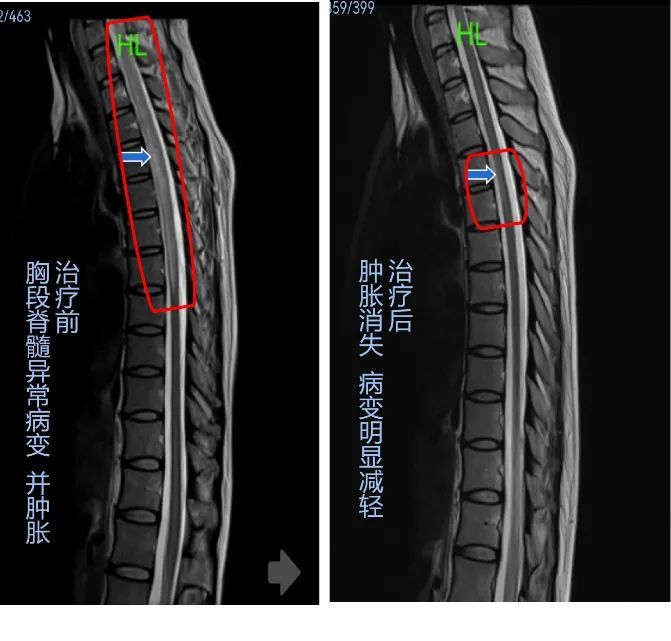

长达15厘米的脊髓发炎,张红鸭医生也有些惊讶,从医十多年,这是她遇到过最长节段的脊髓炎。深知这个病的严重后果,可能会让这个年轻妈妈永远无法照顾自己的孩子,张医生决心竭尽所能。

经过治疗后,赵瑛的病情明显好转。拍片显示,原来发炎的8节段脊髓,已经缩小到2个而且异常信号已经很淡, 抗体指标也大大改善。